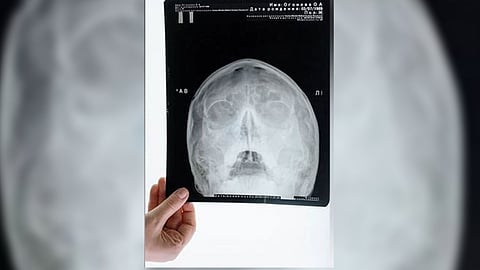

WASHINGTON: Every year, more than 3 million persons 65 and older need emergency room treatment for injuries sustained in falls. Skull fractures are a major consequence of head trauma, which is the most frequent cause of serious damage.

Results of the study, published in the American Journal of Emergency Medicine, showed that when comparing geriatric males and females, males had a significantly increased incidence of skull fracture secondary to head trauma, due mostly to falls. This outcome was unexpected, as previous research has indicated females are more susceptible to facial fractures.